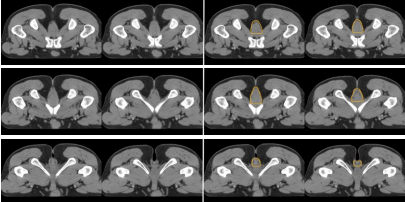

b) GTVnd(粉色) :轉(zhuǎn)移淋巴結(jié)在診斷磁共振或定位磁共振圖像顯示清楚,可參考并輔助在 CT 定位圖像完成 GTVnd 的勾畫(圖 2-圖 4)。

圖 2 直腸癌俯臥位直腸系膜區(qū)淋巴結(jié)勾畫示例

圖 3 直腸癌俯臥位骶前區(qū)淋巴結(jié)勾畫示例

圖 4 直腸癌俯臥位淋巴引流區(qū)淋巴結(jié)勾畫示例